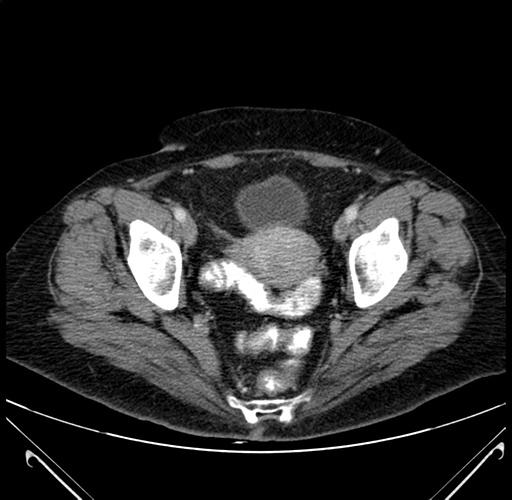

Pre-Chemo: Axial Venous

Axial Venous